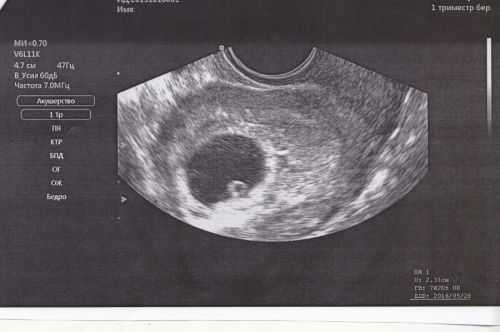

- УЗИ. Метод больше подходит для диагностики цистита. При данном исследовании можно заметить характерные изменения на стенках мочевого пузыря. Беременность диагностируется только через 1,5-2 недели от задержки, когда тесты показывают ее намного раньше. Поэтому, если цистит – первый признак беременности, то отличить ее ультразвуковое исследование не поможет.